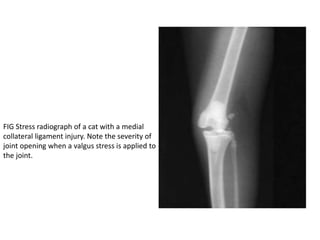

FIG Stress radiograph of a cat with a medial

collateral ligament injury. Note the severity of

joint opening when a valgus stress is applied to

the joint.